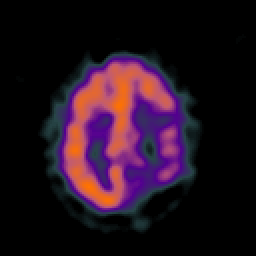

SPECT TC Study #5 -- Slice #39

[Home][Help][Clinical][Tour 1][Tour 2][Tour 3] Slice 39